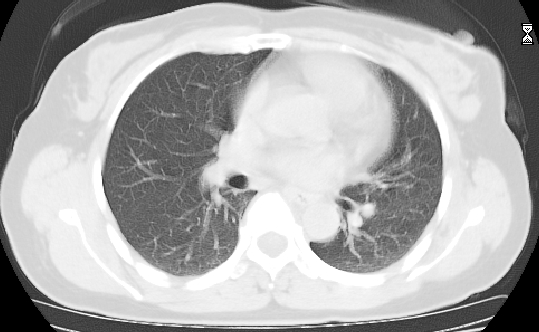

标题: CT25227:背部疼痛伴双侧胸壁痛2月,食欲差。 [打印本页]

标题: CT25227:背部疼痛伴双侧胸壁痛2月,食欲差。

肺结核并胸椎结核?请各位高手指教。

用椎体的条件来扫胸椎呀!考虑1左侧胸膜小结节形成2椎体结核并冷脓肿形成

左肺结核灶,胸椎结核并冷脓肿。

左肺结核灶,胸椎结核并冷脓肿